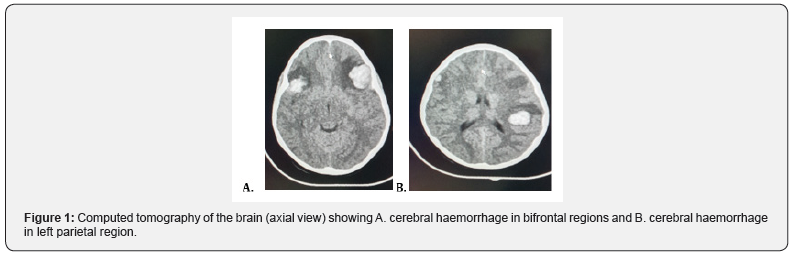

A 6-year-old Afro-Caribbean female, known ITP, presented with a one-day history of a traumatic dislodged tooth with persistent bleed. Approximately 24 hours following the injury, the patient started complaining of headaches. The headaches were described as mild to moderate and was associated with nausea and 2 episodes of vomiting. On initial examination, her Glasgow coma scale (GCS) was 15, with pupils equal and reactive bilaterally. A complete blood count revealed a platelet count of 26 x 109 /L and a computed tomography of the brain without contrast was performed. It showed the presence of the three distinct foci of hyper-densities in keeping with, cerebral contusions. A left frontal lobe contusion of 2.6 cm x 2.3 cm, a right frontal lobe contusion of 1.8 cm x 1.5 cm and left parietal lobe contusion 1.8 cm x 2.3 cm. There was no evidence of midline shift and the dimensions of the ventricular system remained within normal limits. (Figures 1 & 2). Supportive medical management and neuro- observation was commenced with the support of haematology and paediatric medicine. An altered conscious level was noted 12 hours following admission, with a drop in GCS to 9. An urgent blood panel was requested showing a platelet count of 18 x 109 /L. Computed tomography of the brain was repeated. It showed a moderate increase in size of the cerebral contusions. The left frontal lobe contusion measured 3.3cm x 2.7cm, right frontal lobe contusion 2.2cm x 1.9 cm and left parietal lobe contusion 2.3cm x 2.7cm. There was no associated midline shift or ventricle effacement once more (Figure 3).